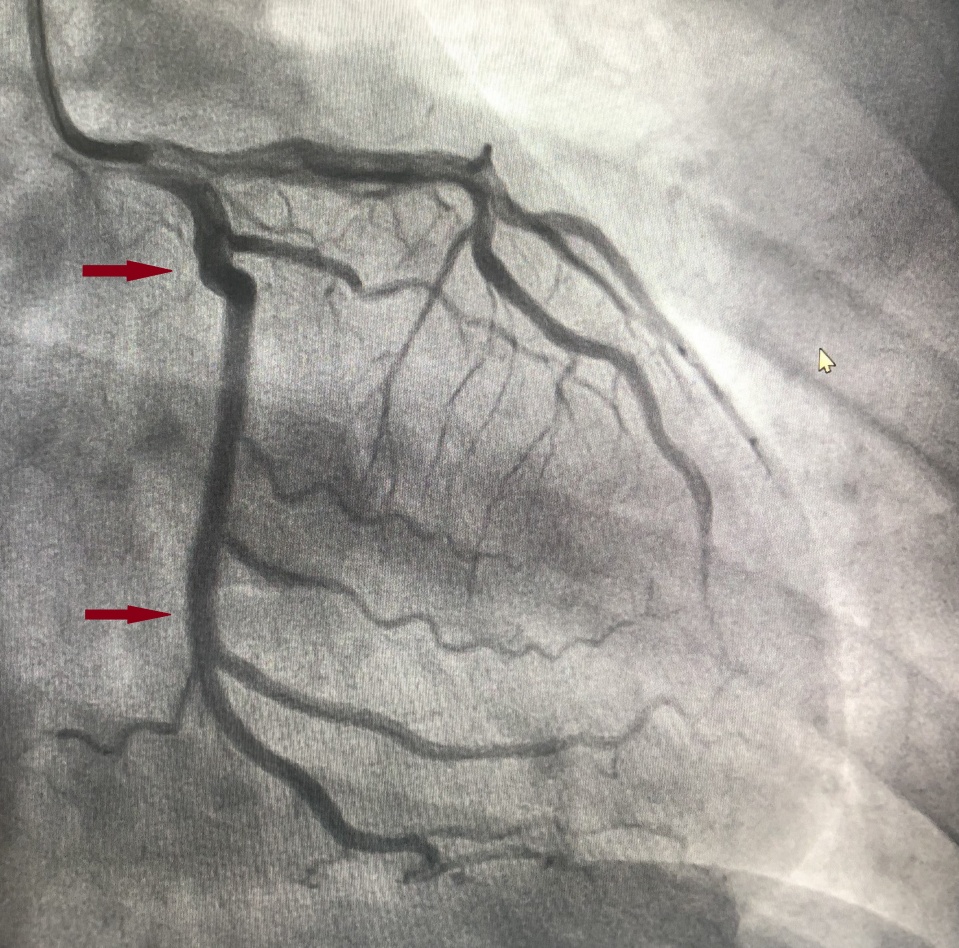

箭头处可见狭窄80%

术中赵军礼主任带领介入团队严格遵循操作规范,使用切割球囊、非顺应性球囊对靶病变进行充分预处理,准确测量靶血管直径。造影显示患者病变较长,需要串联植入2枚BRS才能完全覆盖病变,但BRS支架梁较厚,串联植入既不能重叠,又不能留有空隙,与传统的药物洗脱支架植入要求完全不同,故技术难度较大。